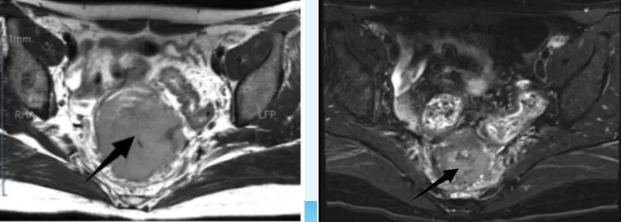

“现在不用喝番泻叶,每天都能正常排便了!”近日,34岁的宫颈癌患者在延安市中医医院(北京大学第三医院延安分院)肿瘤科复诊时难掩喜悦。患者在治疗前,直肠周围巨大转移瘤导致患者无法顺利排便,经过4周期治疗,她直肠7.1cm的巨大肿块已缩小至2.3cm,排便通畅,生活质量得到改善。

1年前患者不幸患有宫颈癌,在外院接受手术后,因未进行后续抗肿瘤治疗,病情逐渐恶化。2025年1月,她出现严重的排便困难,复查发现直肠巨大肿块,依赖番泻叶才能勉强排便。在外院检查发现,肿瘤已发生双肺、肝脏及腹膜后多发转移。经多方打听,来到我院肿瘤科寻求帮助。

入院后,肿瘤科团队对患者进行全面评估,考虑到她较为年轻,耐受能力较好,最终制定了个体化的化疗联合靶向、免疫及中西医结合治疗方案。经过4个周期的规范治疗,不仅肿瘤明显缩小,患者的排便功能也恢复正常,整体状态得到改善。目前,她正准备接受进一步巩固治疗,以稳定病情。